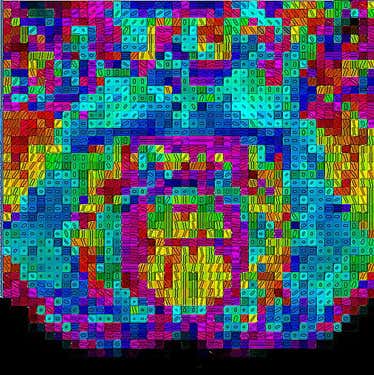

Tapping the spinal cord’s neural hook-up

The colours in this vibrant microstructure MRI highlight how different neural fibres in a mouse embryo’s spinal cord connect the brain to the body.

(Image: UCL CABI)